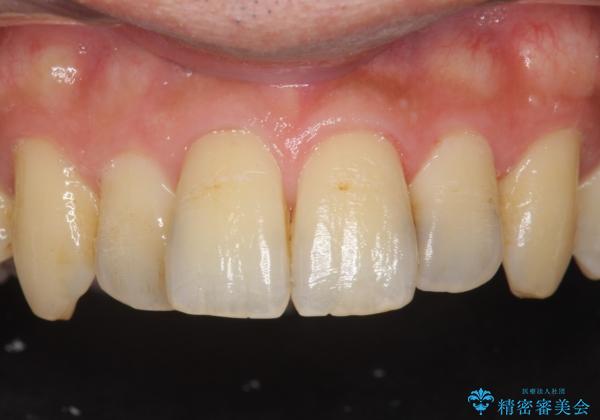

ジルコニアクラウンは表面がツルツルして

汚れ(細菌)や着色がつきにくいです。

ジルコニアクラウンスペシャルはジルコニアクラウンスタンダードに比べ

色のバリエーションが多く、よりご自身の天然歯の色と合うように作れます。

自然な被せ物が入り、大変満足して頂けました。